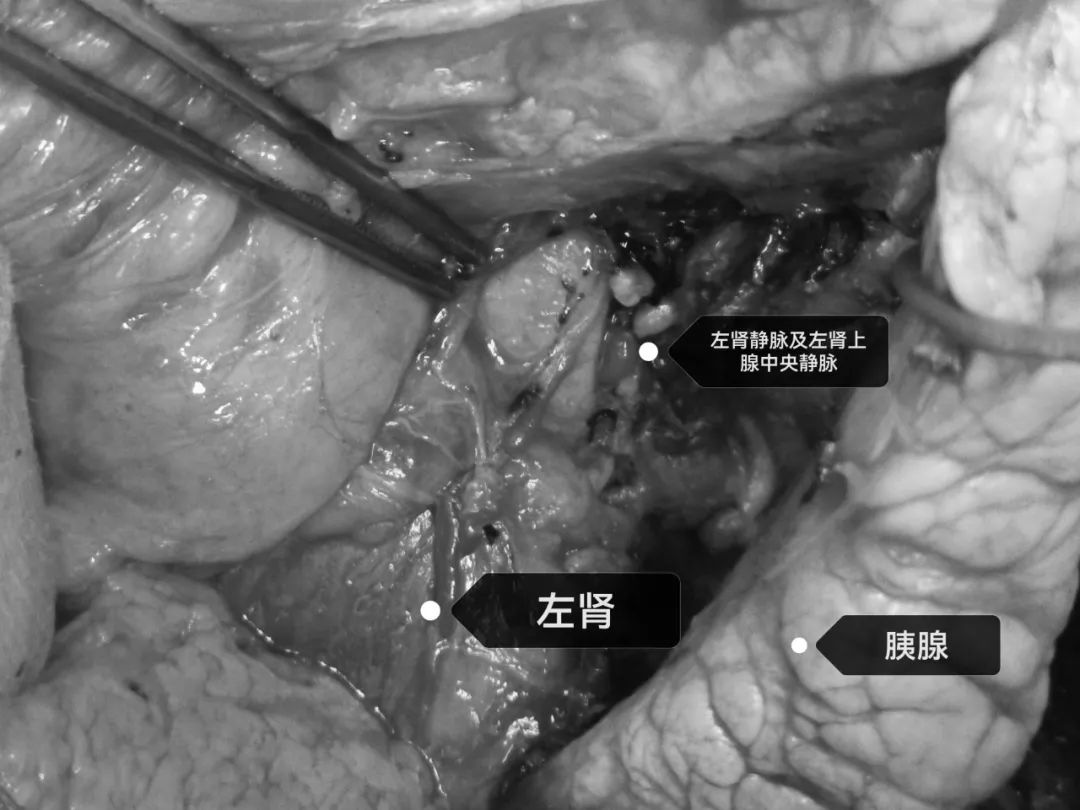

手术团队紧密配合,在腹腔镜下「抽丝剥茧」,小心翼翼剥离肿瘤,肿瘤与周遭脏器关系紧密,剥离肿瘤时精神需高度集中且轻柔操作,避免损伤血管和周遭脏器。无论术前准备多么充分,术中会经历了让人惊心动魄的过程:血压在分离肿瘤时波动剧烈,犹如过山车般时刻牵动着在场所有人的心,大家多次因血压的剧烈波动而暂停手术操作,好在有麻醉团队的保驾护航,三大外科通力协作,顺利将瘤体完整剥离,完好地保护了周围的大血管和器官,完美地避开了术前所预料的风险。

最终在各个科室的共同配合下,最终顺利完成了巨大异位嗜络细胞瘤的切除。待手术完整切除瘤体后,经过仔细检查创面,蒋雷鸣教授长舒了一口气说「患者总算度过了艰难的第一关了「。